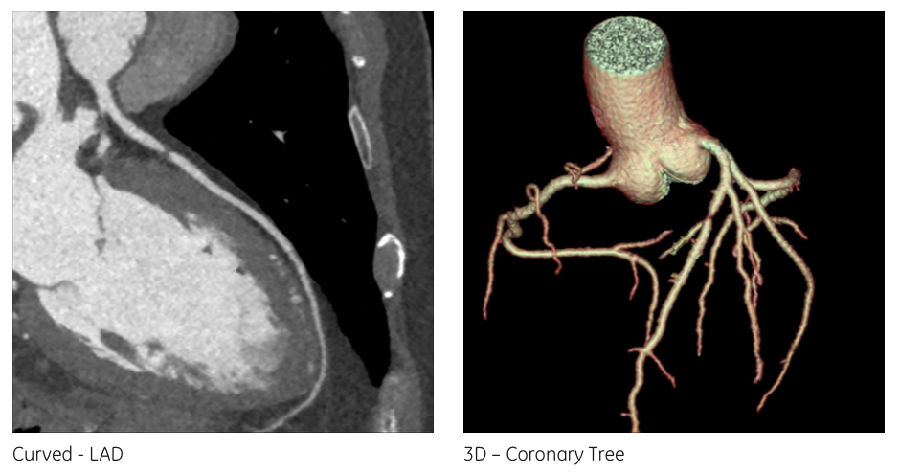

结论 该患者钙化积分为0,但是在CT影像上可以看到左前降支一处90-99%的重度狭窄(图2)。 In this patient with a calcium score of 0, a subtotalocclusion of the LAD & #40;90-99 %& #41; could be visualized on the CT images.

SPECT显示在相应的前壁有一个可逆性灌注缺损区(图3)。该患者进行了冠状动脉造影并确定诊断(图4),之后进行了支架置入术。 Correspondingly, SPECT revealed a large reversible perfusion defect in the anterior wall. The patient underwent coronary angiogramwhere the diagnosis was confirmed and stenting of the lesion was performed.

图2: CCTA 图像